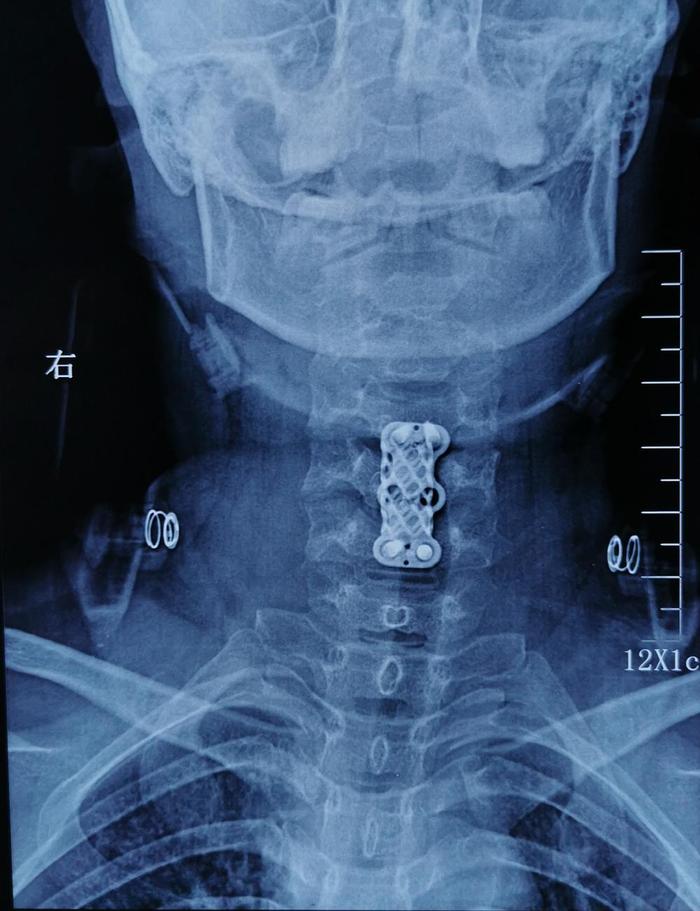

术后影像学资料: